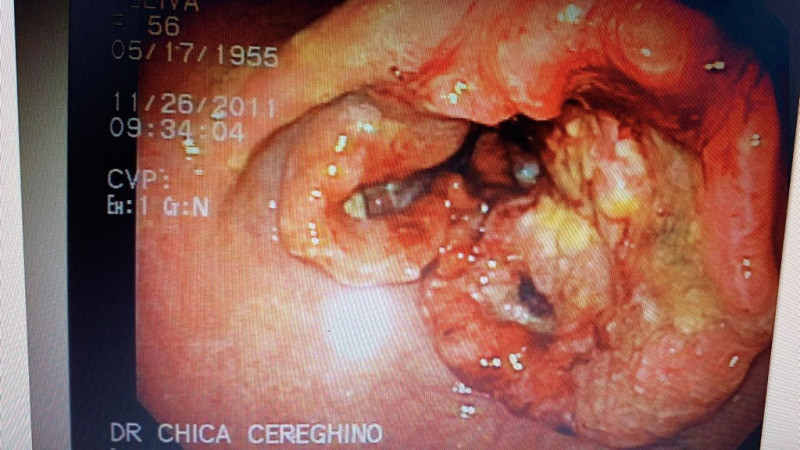

Paciente con cáncer gástrico

Post Image